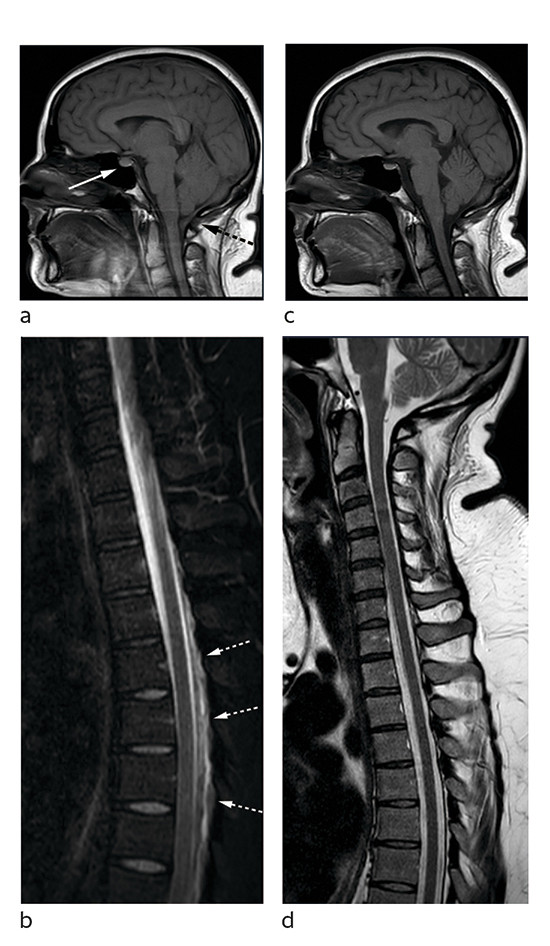

Bildene viser nevroaksen hos en tidligere frisk kvinne i 30-årene. Sagittalt T1-vektet bilde av caput (bilde A) viser forstørret hypofyse (hvit pil) samt at hjernestammen og lillehjernetonsillene har sunket ned mot foramen magnum (stiplet svart pil). Sagittalt T2-vektet, fettsupprimert bilde av cervikotorakalcolumna (bilde B) viser en epidural væskebrem i nivå Th4–Th9 (hvit pil). Det ble også påvist (ikke vist her) fortykkede meninger (FLAIR-serie) og en subdural væskebrem med blodprodukter langs tentoriet (susceptibilitetsvektet serie).

MR-funnene og sykehistorien vekket sterk mistanke om spontan intrakranial hypotensjon (SIH). Pasienten ble i forkant av torakal epidural blodlapp, hvor 20 mL autologt venøst blod ble injisert i nivå Th7/Th8, behandlet med flatt sengeleie og peroral fenazon-koffein og acetazolamid. Prosedyren ble etterfulgt av 24 timers sengeleie med 30 graders senket hodeende (Trendelenburgs posisjon). Hun opplevde god effekt av behandlingen og kunne skrives ut til hjemmet etter tre dager. To måneder senere var hun i betydelig bedring og medikamentfri. Tre måneder etter blodlapp så man normaliserte intrakraniale forhold og kun en beskjeden mengde restvæske i epiduralrommet spinalt (figur C og D).